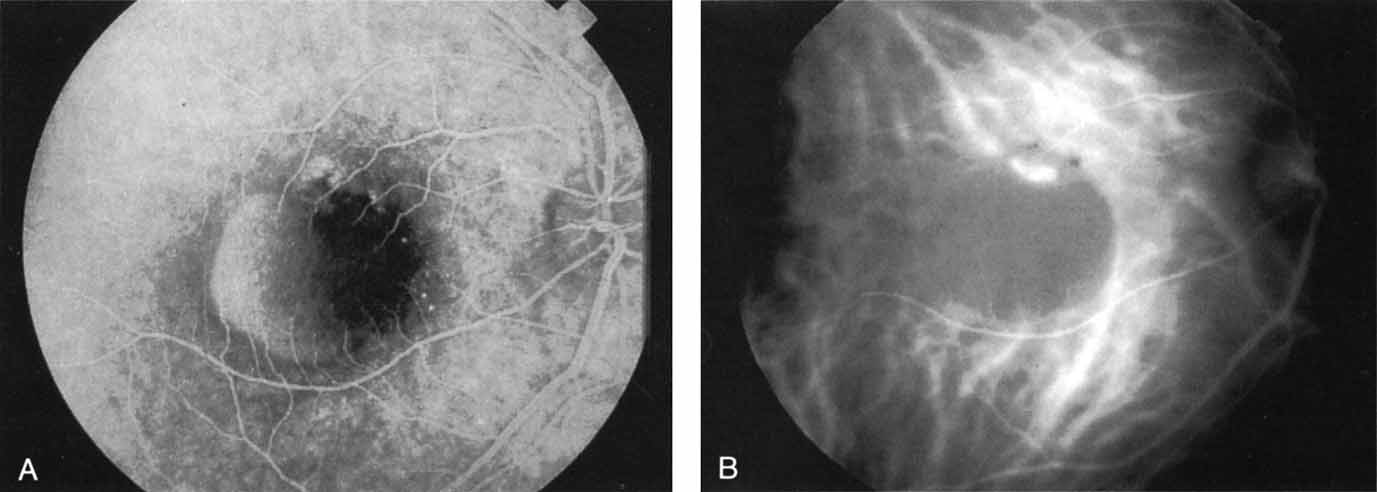

Idiopathic polypoidal choroidal vasculopathy, also known as posterior uveal bleeding syndrome, typically affects darkly pigmented persons who exhibit acute exudative manifestations in the posterior pole, including subretinal hemorrhage and, occasionally, CNV.76,77 ICG angiography facilitates a more definitive diagnosis than fluorescein angiography because it achieves a sharper image of the primary lesion,51,77,78 dilated choroidal vessels terminating in polypoidal or aneurysmal excrescences at the level of the choroid (Fig. 23). These vascular changes account for the secondary exudative and hemorrhagic detachments of the retinal pigment epithelium and neurosensory retina that are characteristic of this disorder. Furthermore, ICG angiography may provide a better means of differentiating the relatively benign aneurysm-like changes at the level of the larger choroidal vessels from CNV, a more devastating secondary manifestation of this chronic disease.79

Fig. 23 A. Clinical photograph of a patient with idiopathic polypoidal choroidal vasculopathy demonstrating the branching lesion at the level of the choroid. There is a more nodular elevation in the inferior macula. A hemorrhagic detachment of the retina is noted temporally in a curvilinear fashion. B. “Green-free” photograph that more vividly demonstrates the branching vascular pattern of this condition. C. High-magnification image of an early-phase indocyanine green (ICG) study reveals filling of the vascular channels at the level of the choroid leading to the polypoidal lesions. Note that the inferior, more elevated lesion, which is nodular on clinical examination, consists of an internal network of branching vessels. D. Late-phase ICG study demonstrates ring-like staining of the small polypoidal lesions. The larger lesion shows intense but nonhomogeneous staining.